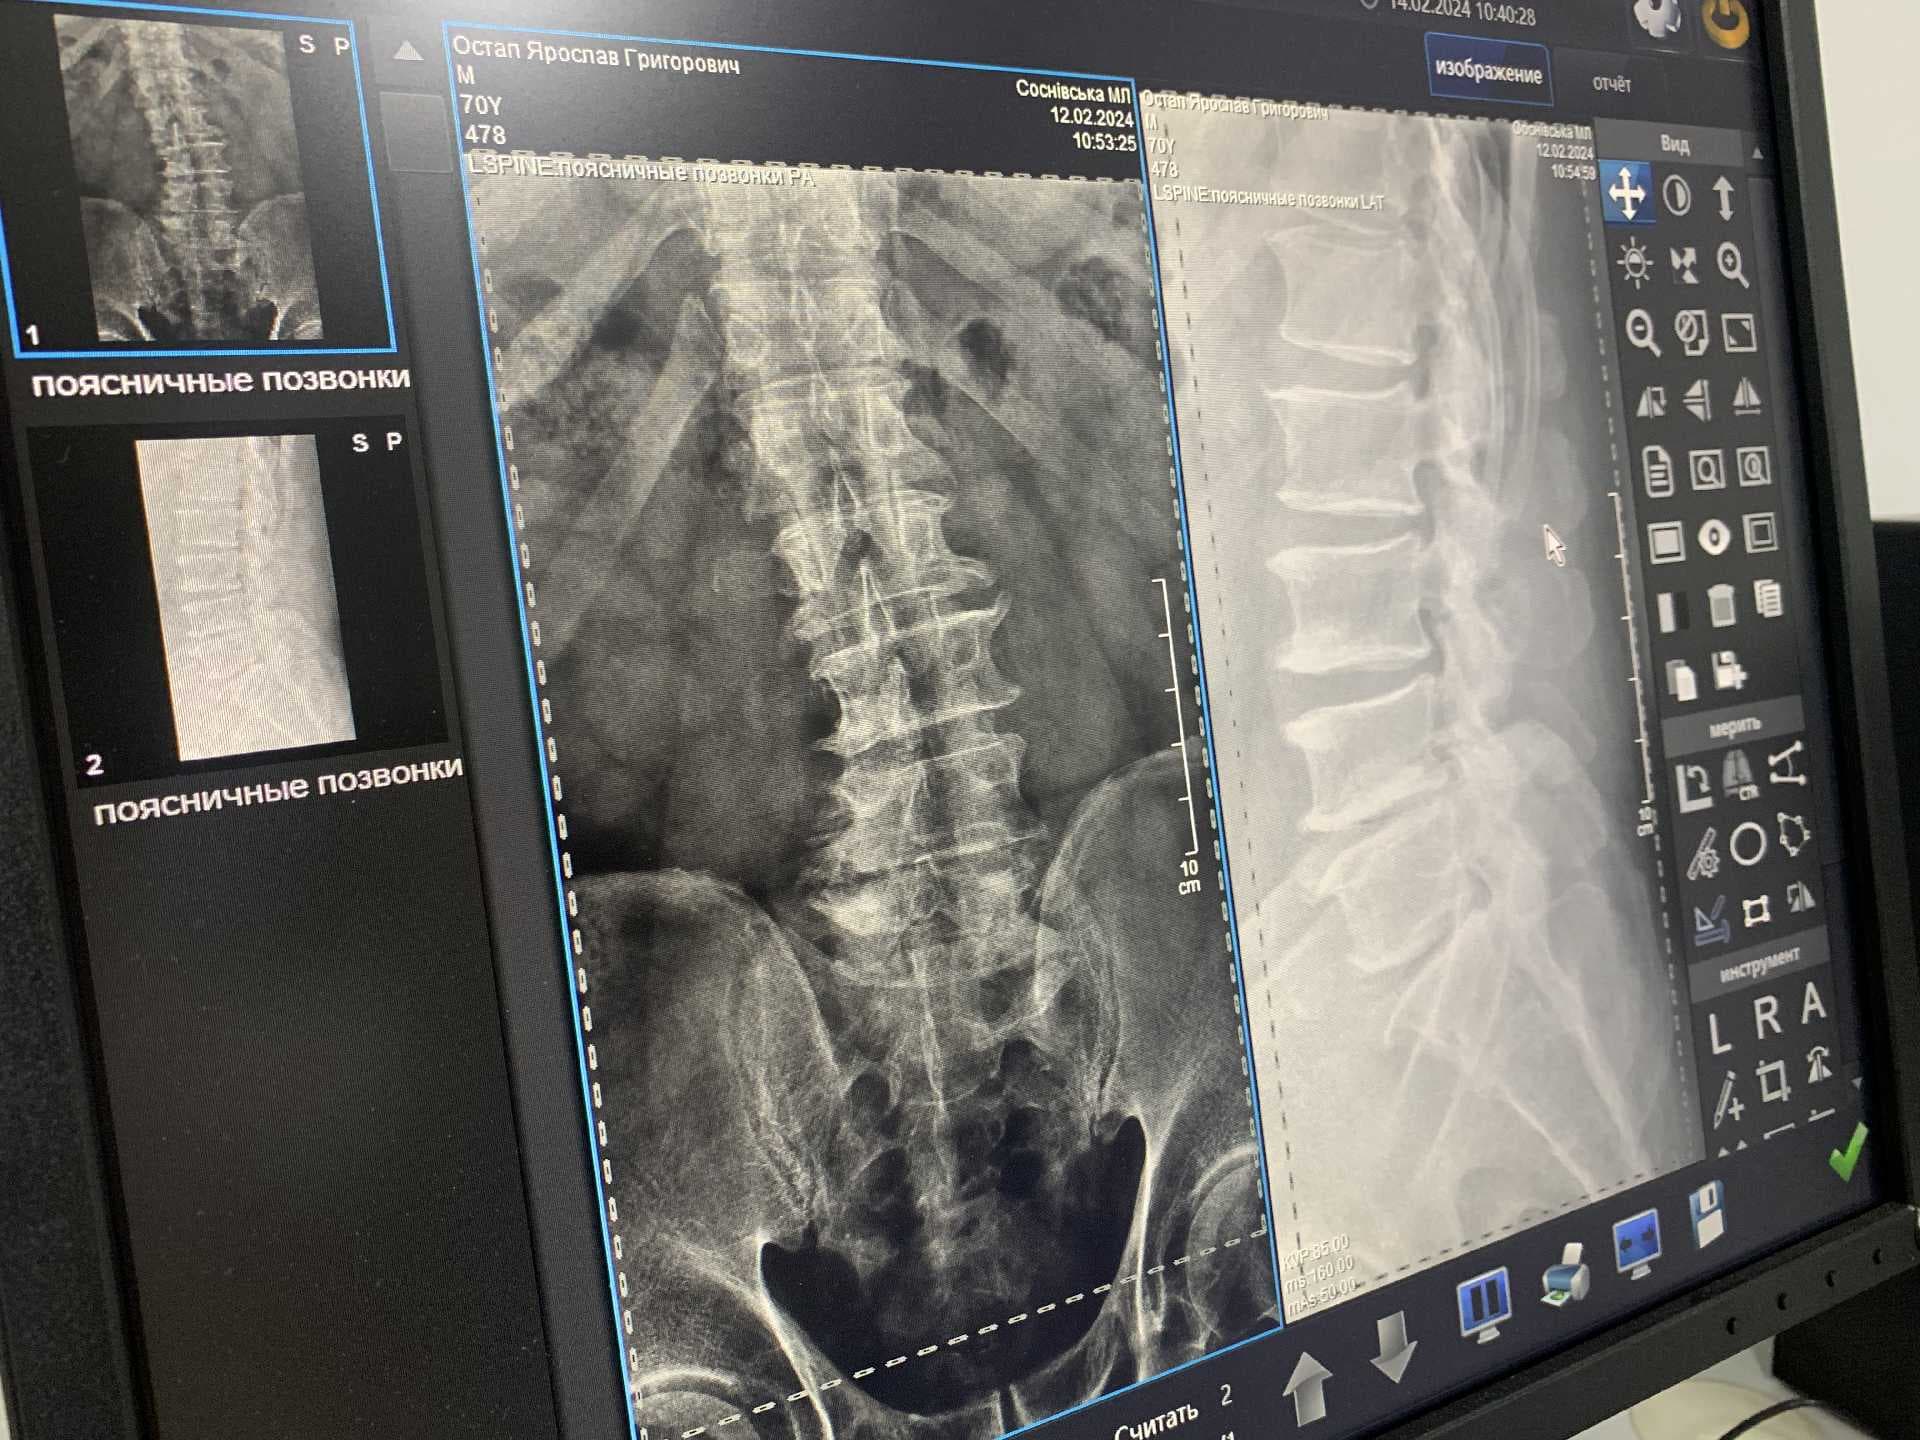

У рентген-кабінеті працює кваліфікований лікар-рентгенолог, молодша медсестра та два лаборанти, які допомагають лікарю в підготовці пацієнтів та обробці зображень. За словами медиків, найбільше людей, що звертаються до них, мають травми кісток, хребта, суглобів, пазух носа та легенів. Для того, аби скористатися послугами рентгену, пацієнтам потрібно мати скерування від сімейного лікаря або іншого спеціаліста.